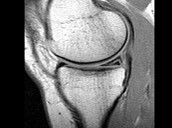

- 单项选择题男,29岁, 左膝关节有外伤史,膝关节疼痛, 活动受限,结合所提供的图像, 最可能的诊断是 ( )

B、前十字韧带撕裂

C、内侧半月板外周后角垂直撕裂

D、内侧半月板后角撕裂

E、后十字韧带撕裂